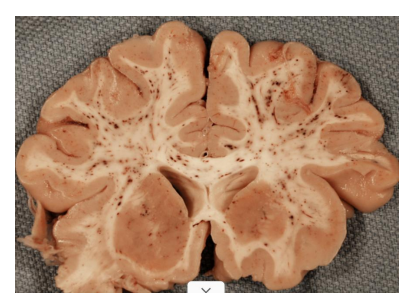

cerebral infract

thrombus